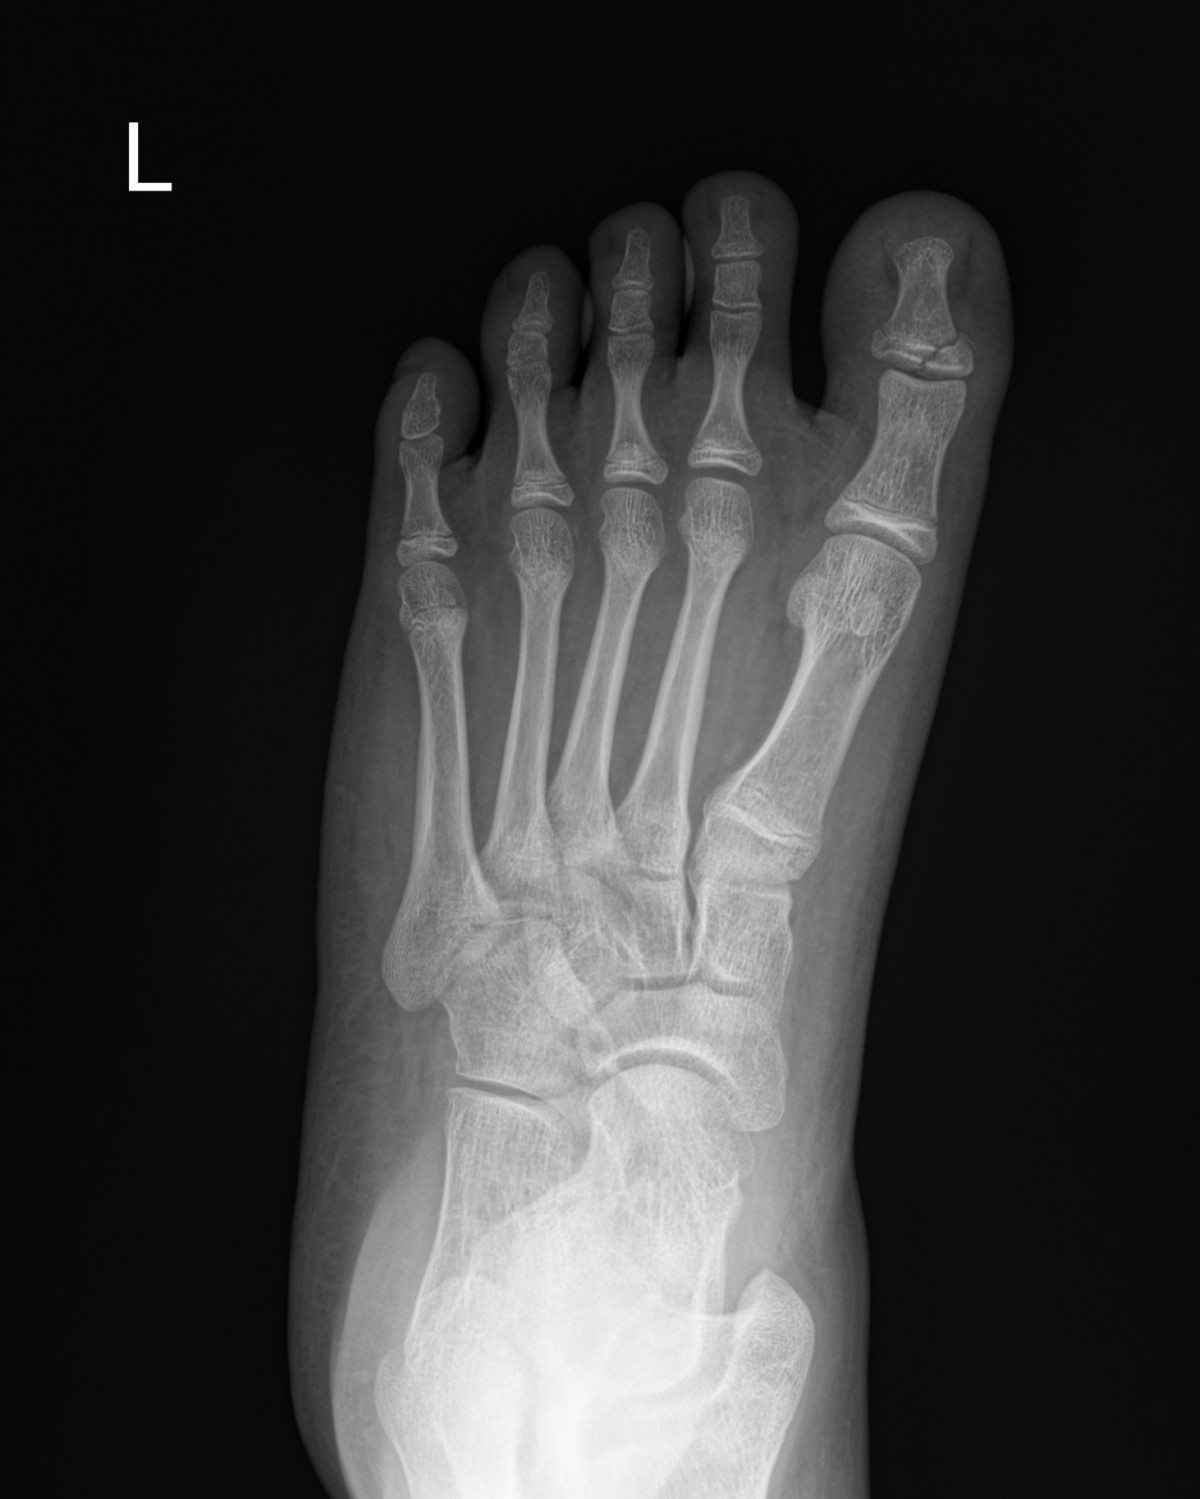

정지영원장님 발가락 골절 수술 김재O 환자

dae765e4d9ac96aee867c9d6292d8784_1758008888_4902.jpg